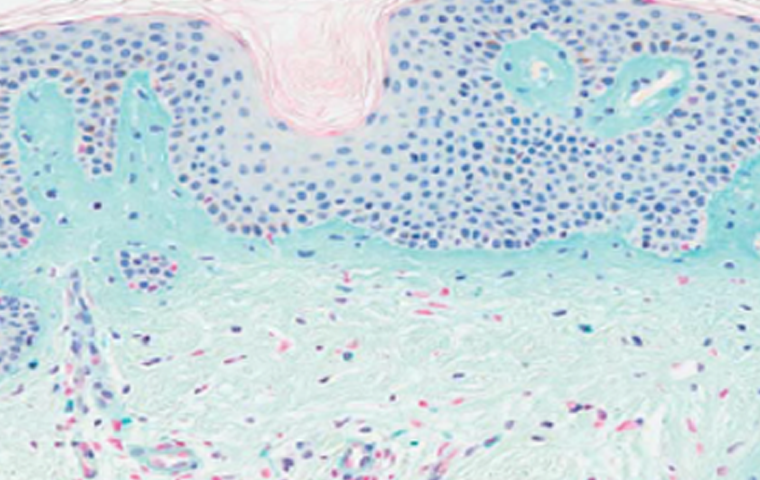

RADIESSE SCIENCE 01

CaHA 성분으로 콜라겐 생성을 유도하는

프리미엄 콜라겐 부스터

레디어스 필러는 주름 부위의 볼륨감을 채워주는 것 뿐만 아니라

체내의 천연 콜라겐 생성을 촉진해주는 효과도 있습니다.

생성된 콜라겐은 시술 후 모양 변화를 최소화하고 지속기간을

길게 유지 해주어 일반 필러에 비해 효과가 좋습니다.

콜라겐 생성 촉진

시술 직후 볼륨감을 주고, 체내 콜라겐 생성을

유도해 효과가 오래 지속됩니다.

CaHA 입자분해

겔은 흡수되고 CaHA 입자는 자연 분해되어

최종적으로 내 콜라겐만 남습니다.